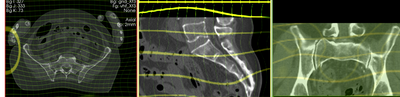

3. Affine Registration

1. Go to the BRAINSfit module

2. select the following parameters:

1. Fixed Image Volume: vhm Moving: vhf

2. check boxes for Include Rigd registr. phase , Include ScaleVersor3D, include Affine

3. Slicer Linear Transform: select "create new transform", rename to "Xf1_Affine" or similar

4. leave rest at defaults. Click Apply

5. registration should take ~ 10 secs.

6. use fade slider to verify alignment; compare with result snapshots shown below. Alignment will not be perfect but should be better than before.